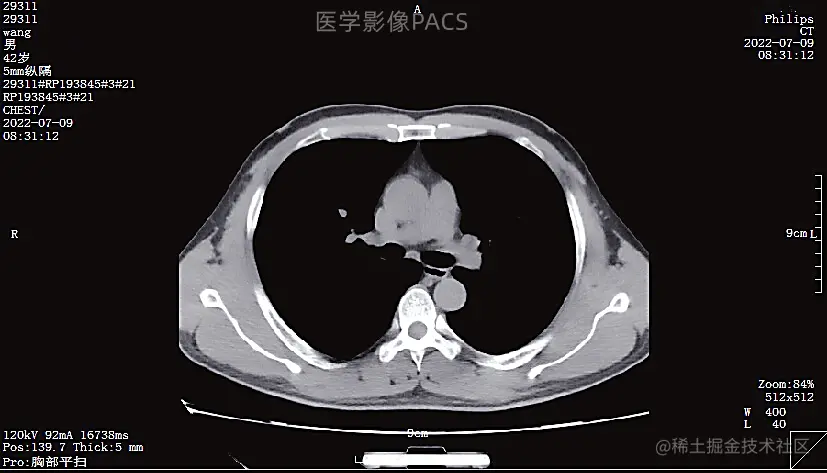

【CT平扫】 获取的是原始数据,可以是横切的水平位,也可以是矢状位和冠状位,多数时候可以很好地建立疾病损伤及对比关系。但是CT平扫对于特殊的部位,如气管和气管拐弯处、肋骨折断后的错位情况,还有其他地方的骨骼或肠腔器官的内部结构,不是特别清楚。所以需要三维重建来还原器官立体处的表现,所以心脏造影、大脑血管造影、气管立体的三维重建、骨骼的三维重建就应运而生。

下面就是我们平时大家所做的CT平扫图像: